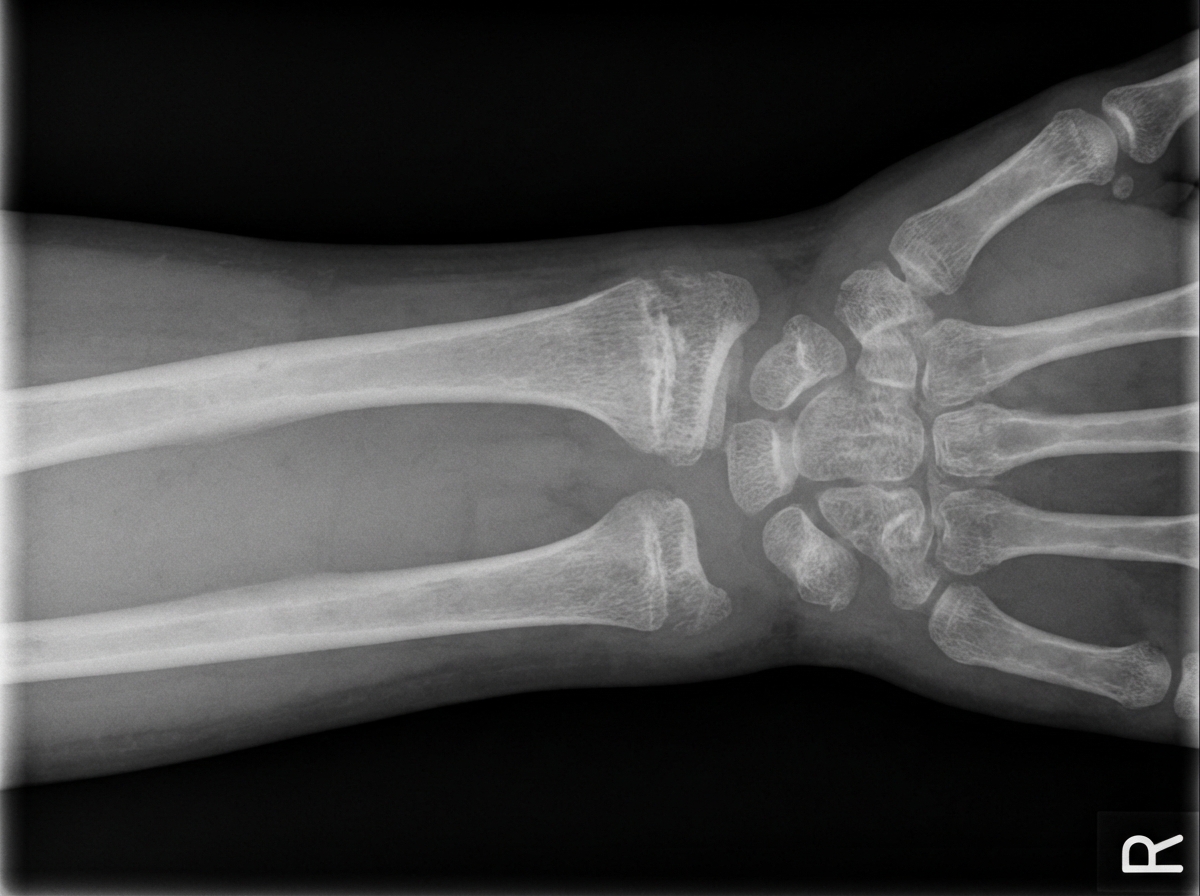

A wrist X-ray is shown. What is the probable diagnosis?

Explanation: ***Rickets*** - Classic X-ray findings include **widened, cupped, and frayed metaphyses** at the distal radius and ulna, indicating defective mineralization. - **Widened growth plates** and **delayed ossification** are characteristic features of rickets in growing children. *Colles fracture* - Shows a **dorsally angulated fracture** of the distal radius with characteristic **dinner fork deformity**. - Would demonstrate clear **cortical disruption** and **fracture lines**, not the smooth metaphyseal changes seen in rickets. *Scaphoid fracture* - Typically occurs in the **waist of the scaphoid bone** and may not be immediately visible on initial X-rays. - Presents with **tenderness in the anatomical snuffbox** and normal metaphyseal appearance of radius and ulna. *Osteoporosis* - Characterized by **generalized bone demineralization** and **cortical thinning** without specific metaphyseal changes. - Does not cause the distinctive **cupping and fraying** of metaphyses seen in metabolic bone disease.